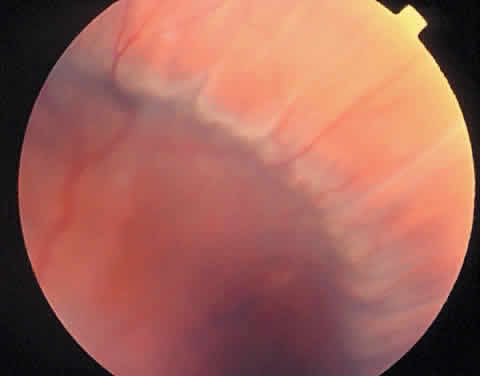

Chorioretinal folds are seen as alternating light and dark striae in the posterior pole, giving the fundus a corrugated appearance (Fig. 2).11 The darker striae correspond to the troughs of the folds where the RPE is viewed “on edge.” The lighter-colored striae correspond with the ridges, where the RPE layer is stretched thin. The width, length, and number of folds are variable. The folds are usually roughly parallel, except in hypotony (in which case the folds are often multidirectional), in a contracted choroidal neovascular membrane (in which case they may be radial), and in optic disc swelling (in which case they may be concentric). Careful biomicroscopic evaluation is helpful in establishing the level of the abnormality in the fundus. The overlying retina is usually uninvolved in isolated chorioretinal folds, although parallel retinal folds can occasionally occur.12

Fig. 2. Choroiretinal folds are typically seen as alternating light and dark striae in the posterior pole. The darker striae correspond to the troughs of the folds where the retinal pigment epithelium is viewed “on edge.” The lighter-colored striae correspond with the ridges, where the retinal pigment epithelium layer is stretched thin.